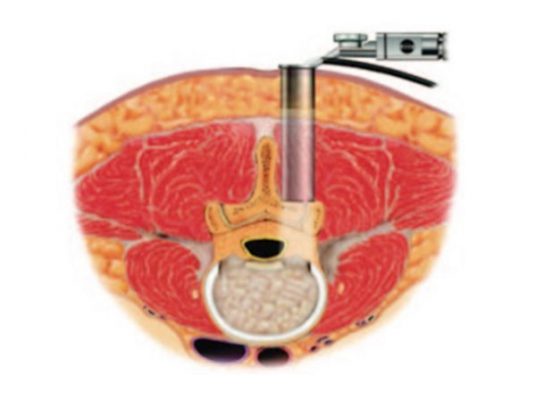

Phẫu thuật cột sống ít xâm lấn (Minimally Invasive Spine Surgery) là các phẫu thuật cột sống sử dụng đường mổ nhỏ và hệ thống ống nong để tiếp cận và sửa chữa các thương tổn bệnh lý của cột sống khác với đường mổ truyền thống.

Mục đích phẫu thuật nhằm giải phóng vị trí chèn ép thần kinh, bảo tồn tối đa cấu trúc mô cơ – xương vốn có của cơ thể người bệnh.